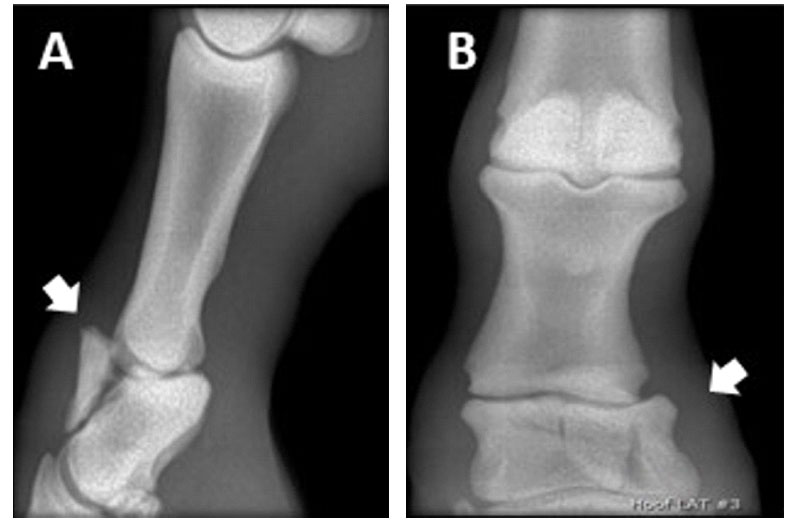

La potranca presentaba claudicación 4/5 durante su remisión y de 3 días de evolución. Se observó inflamación y tumefacción por encima del rodete coronario. Al examen radiológico digital se observó fractura conminuta transversal y vertical de la segunda falange en el miembro anterior derecho (Figura 1).

Figura 1 Estudio radiológico ortogonal de la articulación interfalángica proximal. Se observa una fractura conminuta transversa en la segunda falange